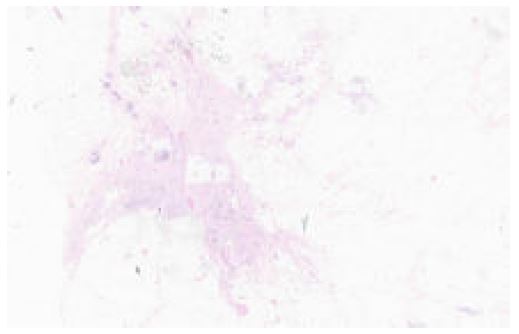

In September 2022, a CT scan of the thorax, abdomen, and pelvis was performed for re-staging. While no pulmonary disease was detected, the scan revealed four suspicious breast nodules (two on each side), as shown in Figure 4. A biopsy later confirmed these nodules to be metastatic sarcoma, identical to the forearm mass, with pathology slides presented in Figures 5 and 6. Prior to the mastectomy, the patient received six rounds of VIT chemotherapy, which included vincristine, irinotecan, and temozolomide. Subsequently, a bilateral mastectomy with partial excision of the pectoralis major muscle was performed in March 2023. The procedure was successful, and no complications were reported. The patient was subsequently referred to physiotherapy.

Figure 5: A section from the affected breast.